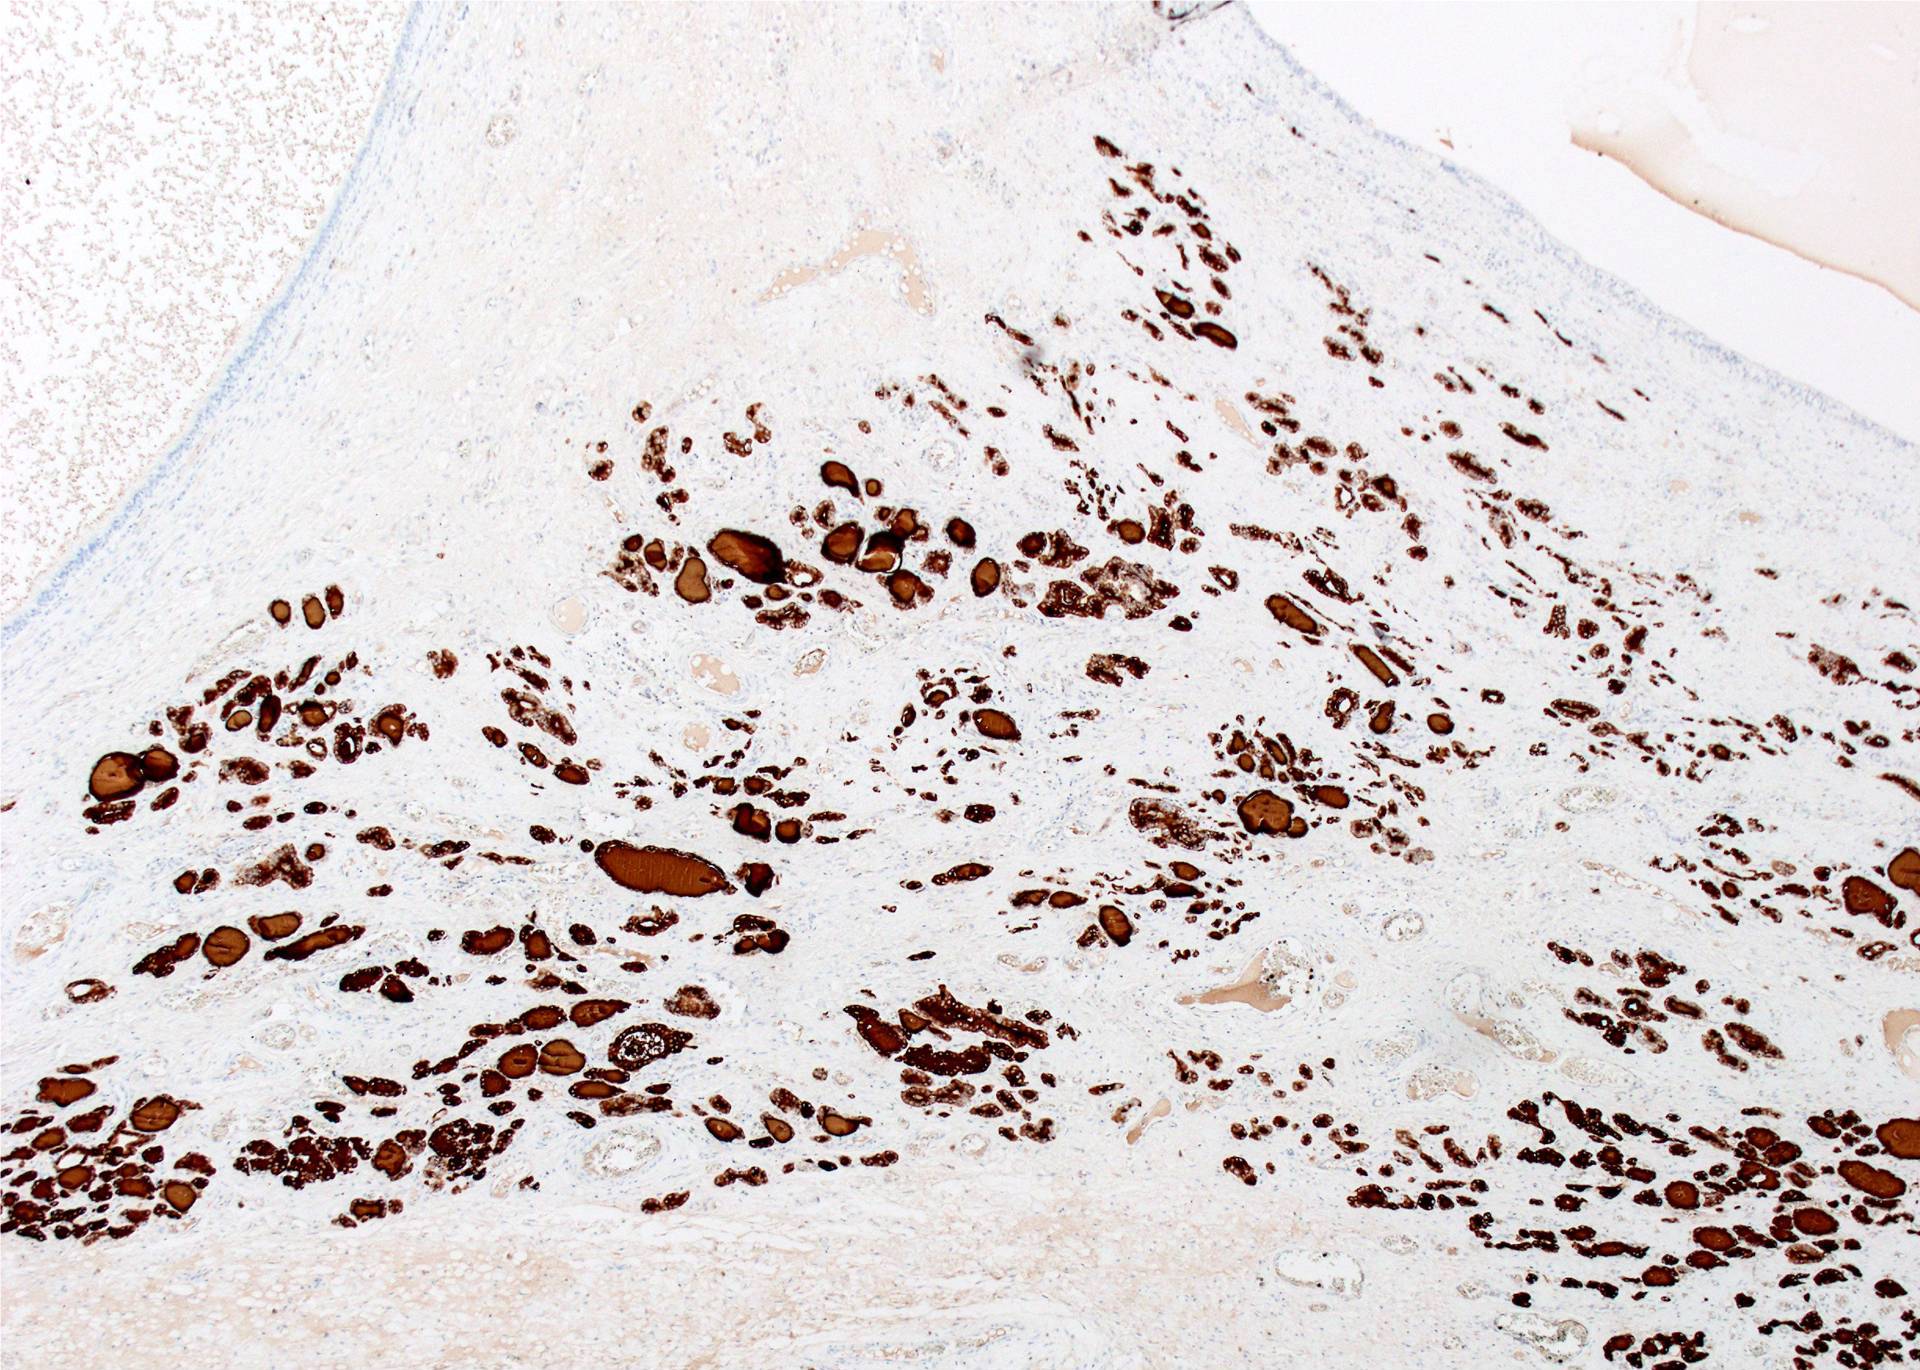

Microscopic (histologic) description

- Type of epithelial lining varies by site, and combinations of the types below can be seen in a single cyst (Head Neck Pathol 2013;7:50):

- Ciliated pseudostratified columnar (respiratory) epithelium in lower neck, perhaps due to its close proximity to upper respiratory tract

- Nonkeratinizing squamous epithelium in higher neck (near tongue and foramen cecum), also can be of metaplastic origin in inflammatory settings

- Stratified cuboidal epithelium at level of hyoid bone

- Very often the cyst is denuded of epithelium, at least focally, which reflects epithelial damage by inflammation

- Secondary inflammation is common, especially in sinus tract (J Pediatr Surg 1984;19:506):

- Intense lymphocytic infiltration, rarely arranged into lymphoid follicles

- Admixture of neutrophils (if the cyst is infected)

- Granulation tissue and fibrosis

- Thyroid follicles in the cyst / duct wall:

- Found in 30% - 60%, with higher yield on serial sections

- More common in infra- versus suprahyoid remnants, on the right paramedian side (Ann Otol Rhinol Laryngol 2000;109:1135)

- Seen in small irregular groups

- Thyroid epithelium may be normal or rarely hyperplastic or neoplastic

- Thyroid tissue often hidden by inflammation (Laryngoscope 2001;111:1002)

- Absence of thyroid tissue does not exclude the diagnosis of TGD cyst

- Mucous salivary-type glands can be found in the cyst wall, frequently in lingual and suprahyoid locations (Ann Otol Rhinol Laryngol 1996;105:996)

Microscopic (histologic) images

Contributed by Andrey Bychkov, M.D., Ph.D., Mark R. Wick, M.D. and AFIP